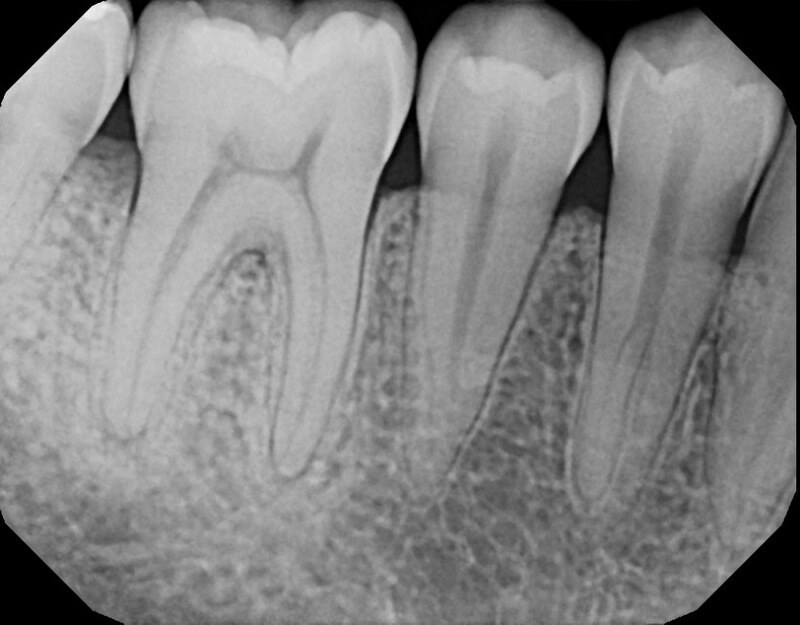

Дентальные снимки и диагностика кариеса